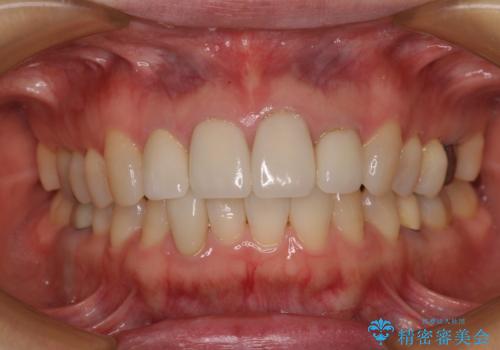

- 上顎4前歯に装着されているセラミッククラウンのうち、ひとつが欠けてしまったとのことで来院された患者様です。

土台となっている歯には問題がないため、周囲のセラミッククラウンと色調が合うように、オーダーメイドタイプのセラミッククラウンにて補綴治療を行うこととしました.

欠けてしまったセラミッククラウンはガラス系セラミッククラウンであったため、今回製作する歯は、強度の強いジルコニアセラミッククラウンとしました。

クラウンの種類は異なりますが、色調の適合したクラウンを装着することができました。